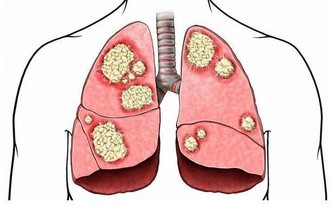

引起腮腺炎的原因有很多,日常比較常見的為細菌或病毒感染。微生物感染導致腮腺部分出現紅腫熱痛的症狀,全身表現主要為發熱。血常規檢查可見中性粒細胞升高,疾病發展後期會有膿液自腮腺導管流出。病毒性腮腺炎多見於腮腺炎病毒感染,具有一定的傳染性,沒得到及時處理的腮腺炎還可能導致全身其他部位的繼發感染,需要引起重視。